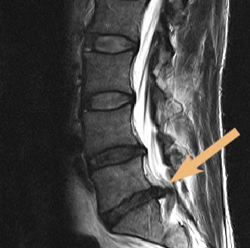

Der Bandscheibenvorfall

http://www.betaklinik.de/wp-content/uploads/2014/07/Bandscheibenvorfall_sagittal.jpg

Dies ist ein Sonderfall bei Rückenschmerzen. Die Diagnostik sollte über den Hausarzt und auf jeden Fall über Fachärzte erfolgen. Die Diagnostik umfasst die Anamnese, die körperliche Untersuchung, die neurologische Untersuchung und radiologische Untersuchung evtl. mit Bildschnittdiagnostik (Computer Tomographie CT oder Magnet Resonanz Therapie Kern Spin MRT).

Die wichtigsten Zeichen finden Sie bei den sogenannten Red Flags oder auch Alarmsymptomen genannt. Hinweise auf einen Bandscheibenvorfall geben Lähmungen, Gefühlsstörungen oder Muskelschwäche sowie zunehmende Schmerzen.

Nicht jeder Bandscheibenvorfall wird operiert. Die Operation bietet in der Hälfte aller Fälle die Chance beschwerdefrei zu werden. Daher sollte die Indikation zur Operation von einem erfahrenen Arzt gestellt werden. In vielen Fällen kann man über die obengenannten Maßnahmen sehr viel erreichen. Es gibt allerdings auch Fälle, bei denen eine Operation unbedingt vorgenommen werden und nicht verschleppt werden sollte.

Viele Menschen haben Bandscheibenvorfälle und wissen nichts davon, weil sie keine Beschwerden haben. Daher kann es in Einzelfällen auch geschehen, dass Rückenschmerzen auftreten, ein Bandscheibenvorfall diagnostiziert wird und dieser war schon lange vor den Rückenschmerzen vorhanden und ist gar nicht die alleinige Ursache der Beschwerden.